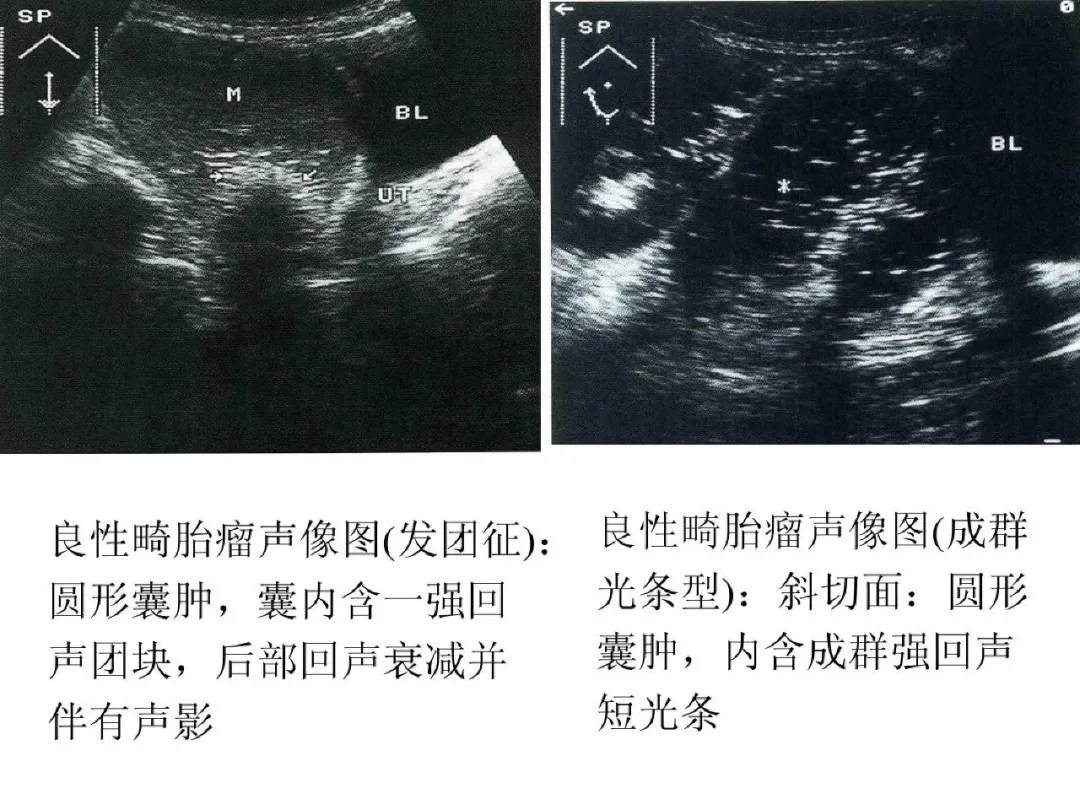

良性畸胎瘤与恶性畸胎瘤

●良性畸胎瘤超声特点:圆形或椭圆形,多为单侧;壁厚,清晰或不清;囊内显示飘浮光点,如面团征、发团征、脂液分层征;内可显示强回声光团、光带。